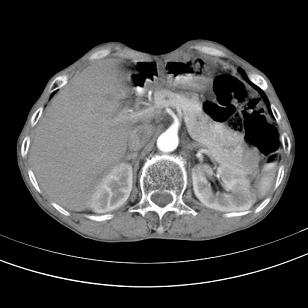

标题: 男,65岁,反复右上腹痛, [打印本页]

标题: 男,65岁,反复右上腹痛,

胃镜提示十二指肠占位